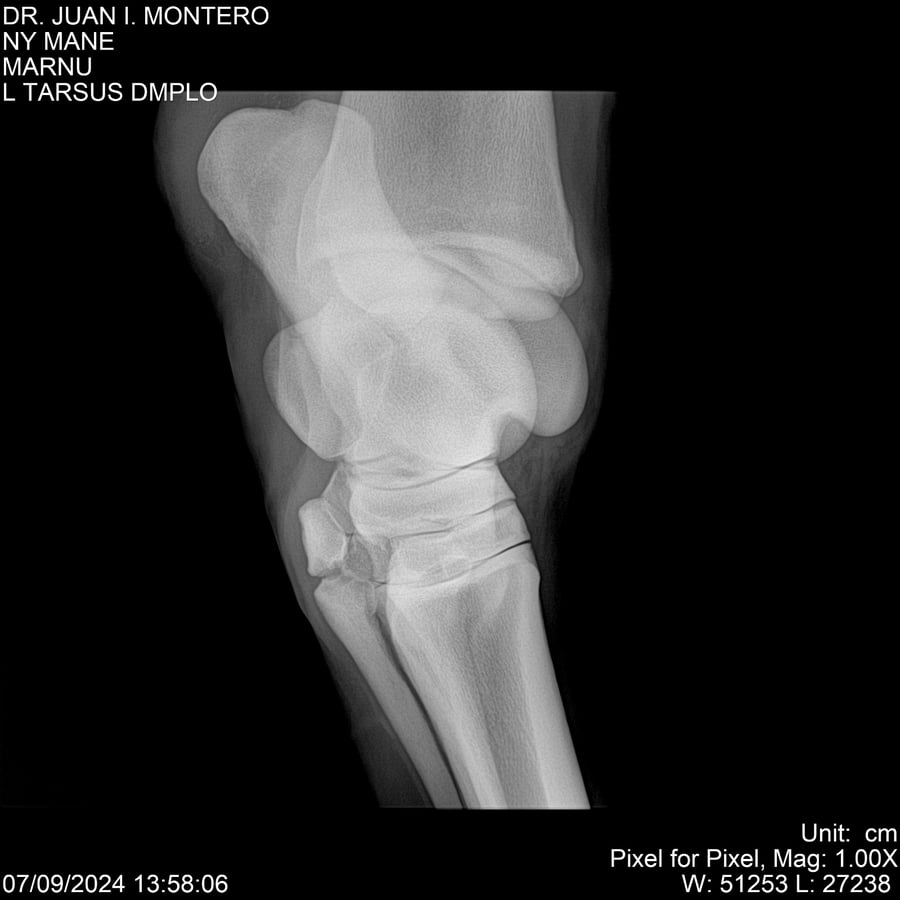

LOTE 20, NY MANE Lote Anterior Volver al remate Lote Siguiente Ficha Contacto Montevideo - Ficha del Lote Identificador: #282520 Categoría: Yeguarizos 76 Visualizaciones ClicData Contacto Empresa: Abelenda N. R., Walter Hugo Nombre*: Teléfono* : E-mail* : Mensaje Enviar Registrese gratis Este contenido Exclusivo está disponible sólo para usuarios registrados Ingresar